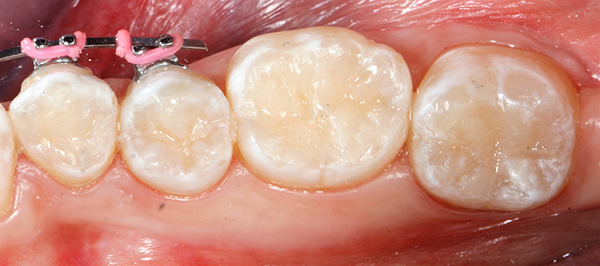

Final polish was achieved with a Kerr ProGloss™polisher (Fig. 9). ProGloss polishers are a one-step polishing system for all types of composite restorations. With the ProGloss polisher, one can achieve a faster, higher surface luster in one simple procedure, as seen in Figure 9.

The case was completed and the patient was very happy with the beautiful results, indistinguishable from her surrounding natural dentition, even with great magnification (Fig. 10).

Fig. 9 Fig. 10